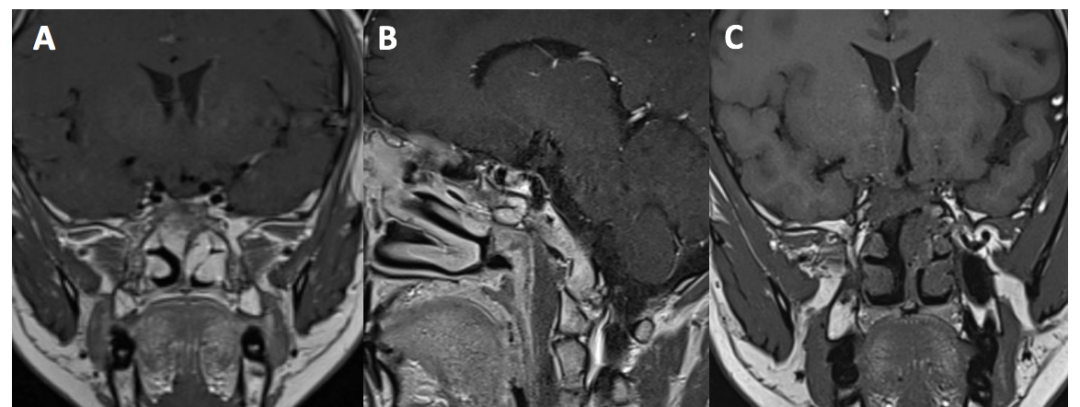

术后病理回报:垂体腺瘤。结合免疫组化及特殊染色结果,符合促性腺激素细胞腺瘤。免疫组化结果:ACTH-,Prolactin-,GH-,FSH-,LH+,TSH-,ER -,PIT -1+,SF-1+,T-PIT-,SSTR2-,P53-,Ki-67 1%+,Syn+。特殊染色结果:PAS-,网状纤维染色,网状纤维破坏(图3)。

图3. 术后病理:垂体腺瘤。